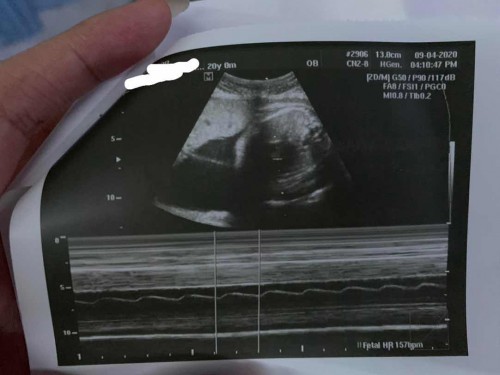

Hello po ask kolang ano kaya posisyon ng baby ko dto? 8mos preggy hehe tia

nasa diagnosis or result po nito ng ultrasound nyo nakalagay kung ano position ni baby, malaki na si baby at 8mos so bale parte lang makukuhaan ng sono (gaya ng nakikita nyo sa pic) di tulad nung nasa 1st trimester na buong katawan makikita agad :)